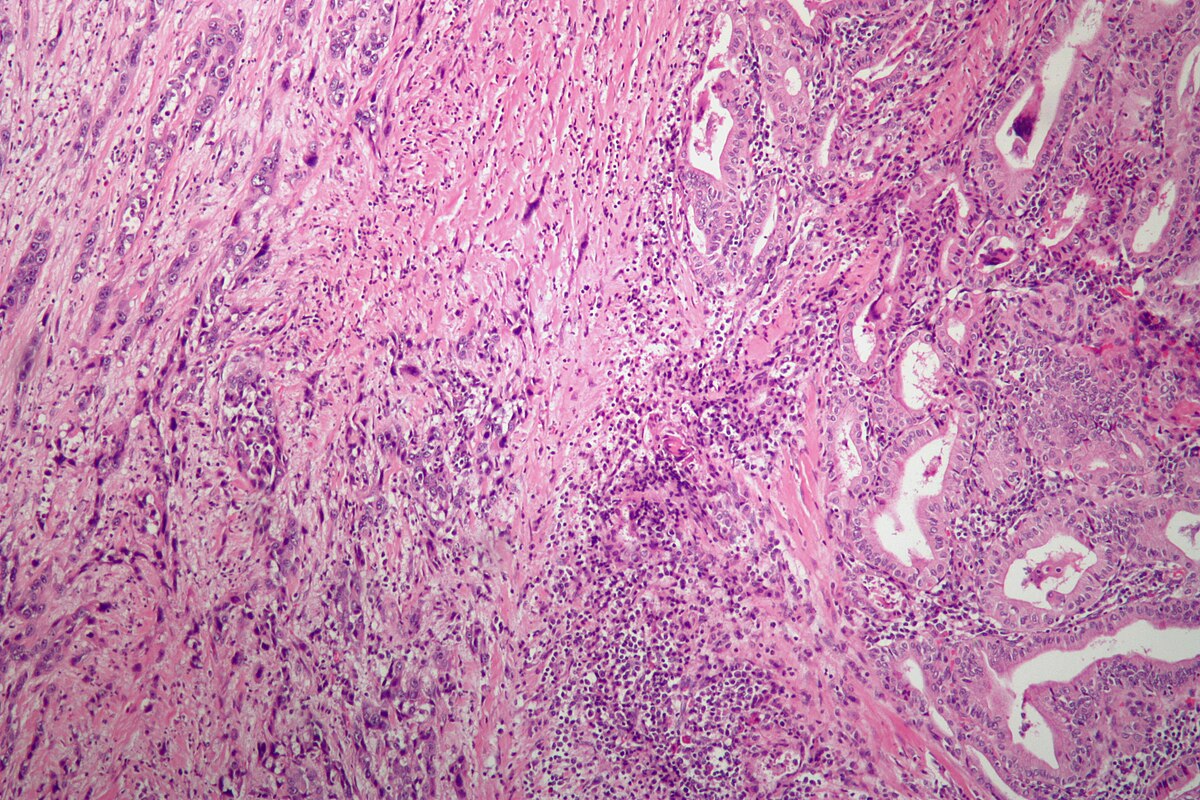

Фотографии опухоли медуллярной аденокарциномы